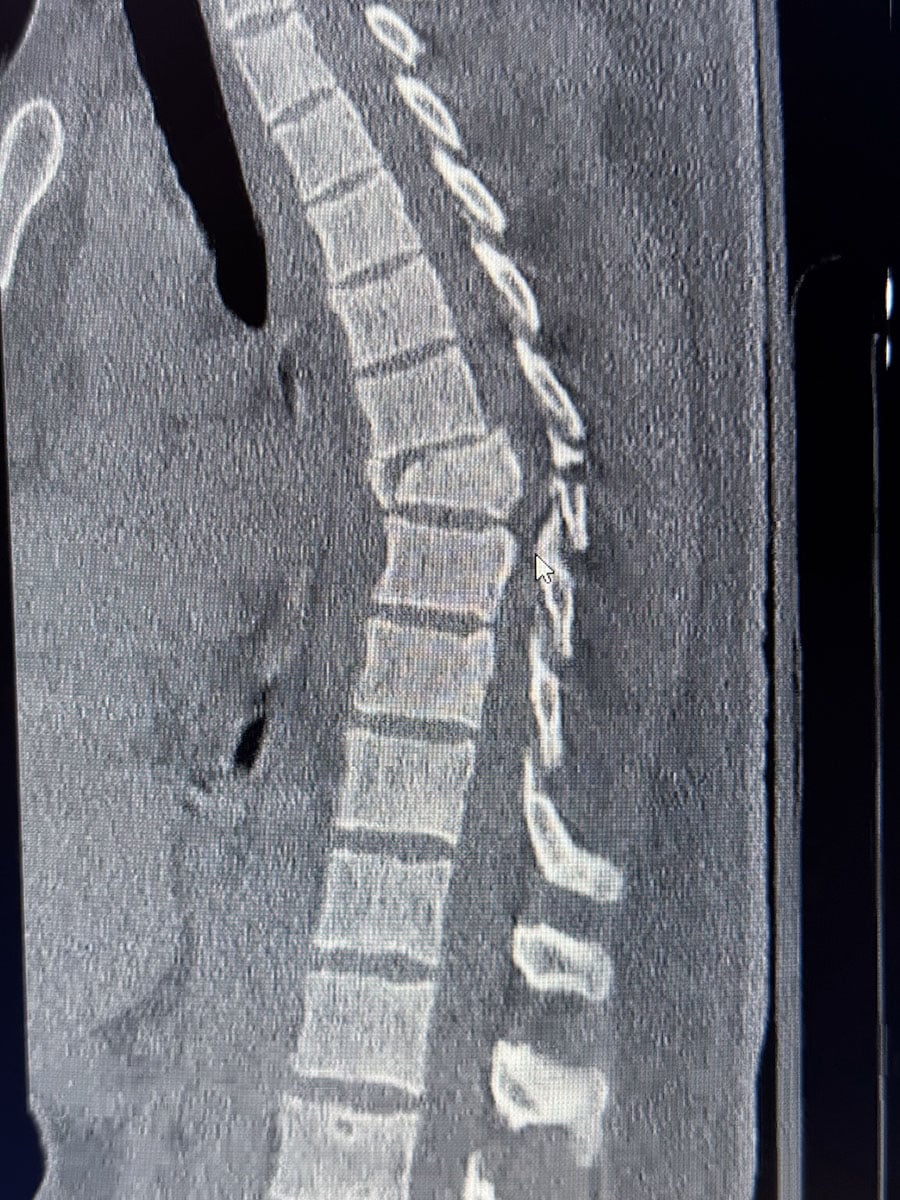

Upon arrival, Chad was diagnosed with a serious spinal injury: a burst fracture at T7-T8, a spinal cord contusion, and multiple rib fractures. The injury caused a significant loss of sensory and motor function below the T8 vertebrae, resulting in paralysis from the belly button down. Chad also suffered a stable C3 fracture that will be treated conservatively with a cervical collar.

On February 23, 2025, Chad underwent a 5.5-hour surgery performed by Dr. Matthew Lawson, a highly respected spinal surgeon. The procedure included posterior thoracic stabilization, decompressive laminectomy, open reduction of the T8 fracture, and other complex spinal operations to stabilize his spine.